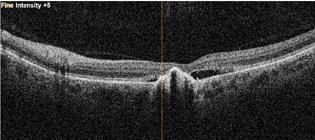

L’examen du fond d’oeil révèle une maculopathie centrale OU de stade V (atrophique) (Figures 1 et 2). À l’OCT il y a accumulation de liquide entre l’EPR et les photorécepteurs en plus d’une zone atrophiée centrale OD et de changement à l’EPR OS (Figures 3 et 4).